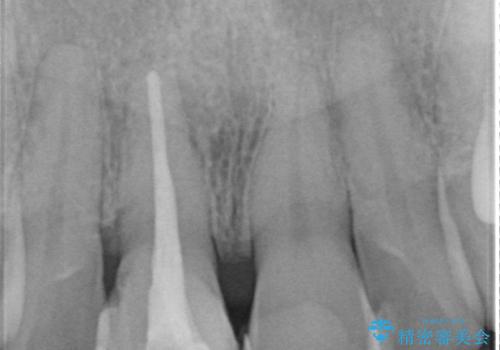

根管治療を行いそのままにしていると歯は、徐々に変色を来します。

感染の疑われる根管内に対し再度根管治療を行い、セラミッククラウンを作製することで審美性の回復します。